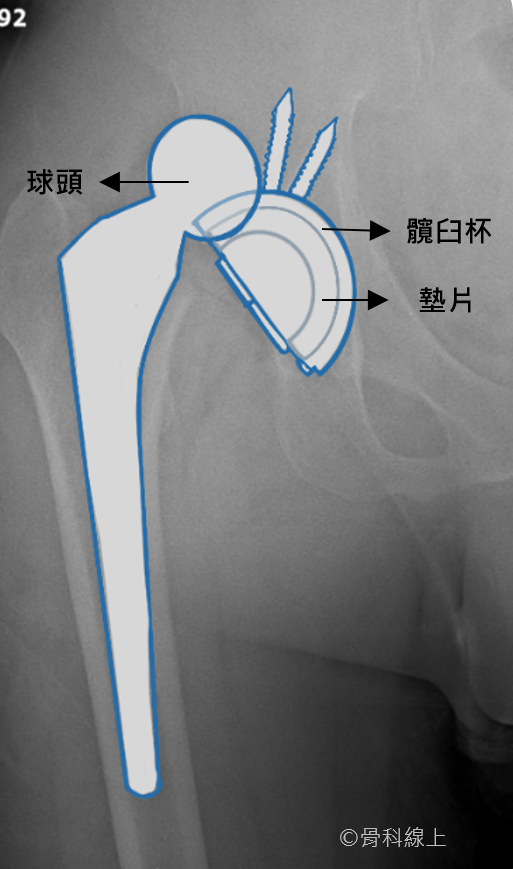

脫臼的 X 光【球頭脫離髖臼杯】

而雙動式人工髖關節(dual mobility total hip arthroplasty)的設計,簡單來說,是把聚乙烯墊片做成另外一個球頭(大頭, shell),套在原本的髖關節球頭(小頭, head)上,所以小頭與大頭間可以活動,大頭與髖臼杯間也可以活動,也就是所謂 “雙動”(dual mobility)的名稱由來。正因為大頭的直徑大小遠超過一般人工關節球頭,脫臼的機會就可以大幅下降。

雙動式人工髖關節的球頭較大,除了增加跳躍高度,有效的降低脫臼的機會,理論上也增加了髖關節的活動角度(示意圖)。

雙動式人工髖關節